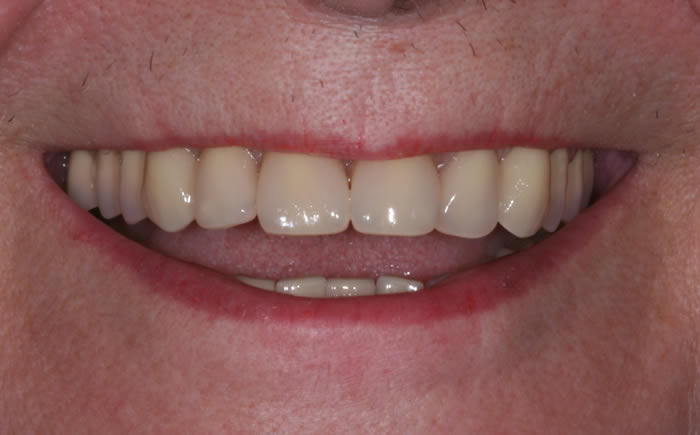

Missing upper front tooth replaced by dental implant and crown